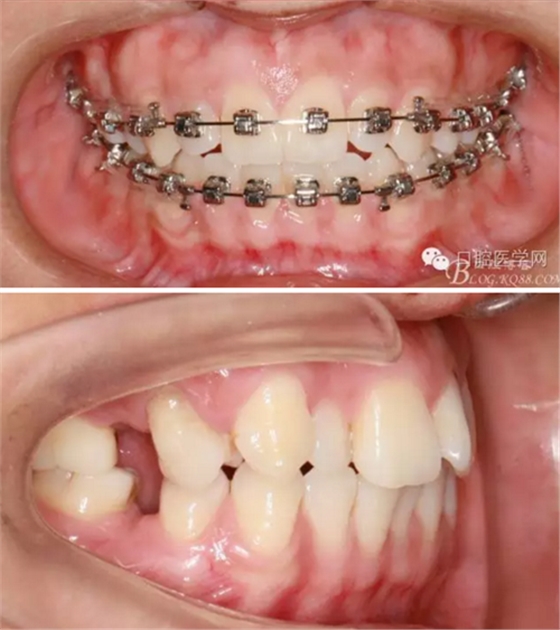

37,45缺失后,鄰牙近中移動(dòng)占據(jù)了部分牙位;患者要求減少治療費(fèi)用,不做種植修復(fù),那怎么協(xié)調(diào)右側(cè)的咬合關(guān)系?

在滿足功能的前提下,退而求其次...有時(shí)候,正畸醫(yī)生不得不妥協(xié)。